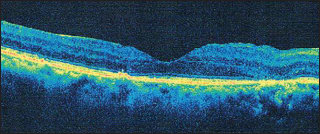

My second example is an 80-year-old woman with DME in both eyes (Figure 3, Page 55). Again, I had previously administered multiple injections of intravitreal bevacizumab and triamcinolone. However, the DME had not responded to the anti-VEGF therapy, and her central retinal thickness was 403 μm, with visual acuity of 20/60.

Figure 3. This is 80-year-old woman had refractory DME that did not respond to anti-VEGF or steroid. Central retinal thickness was 403 μm.

I performed MPLT with 500 mW of power, 200 msec, with a 5% duty cycle. I applied repetitive micropulses in a dense treatment pattern over the edematous area as shown by OCT. Three weeks post-treatment (Figure 4), the central retinal thickness had reduced to 159 μm, and visual acuity had improved to 20/50.